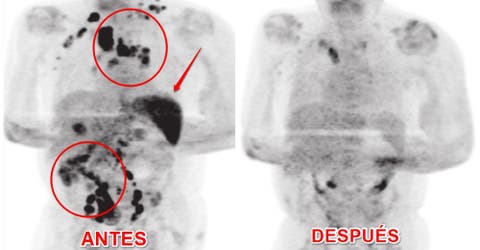

Según el reporte de los médicos, cuatro meses después, notaron que se había reducido la inflamación de los ganglios. Después de realizarle una exploración por tomografía PET, comprobaron que las lesiones causadas por el cáncer habían desaparecido casi en su totalidad.